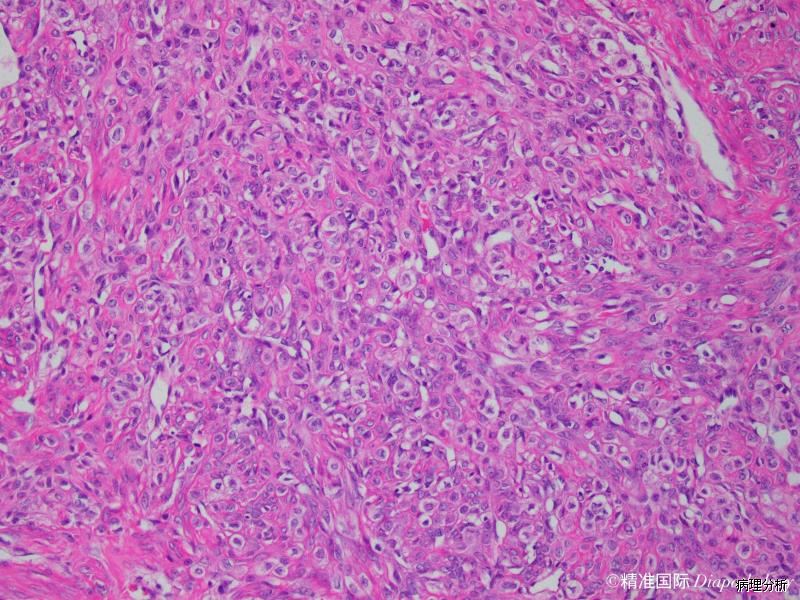

良性肿瘤,表现为在细胞稀疏、水肿或胶原背景上圆形与梭形细胞密集混合增生形成结节。

3. 典型特征是致密的胶原化或水肿样少细胞区将细胞丰富区分隔成结节状,似分叶状;

4. 结节内纤维母细胞和圆形、空泡样、印戒样细胞杂乱无章地分布;

6. 结节内可伴有硬化,有些结节内可见明显的薄壁血管;